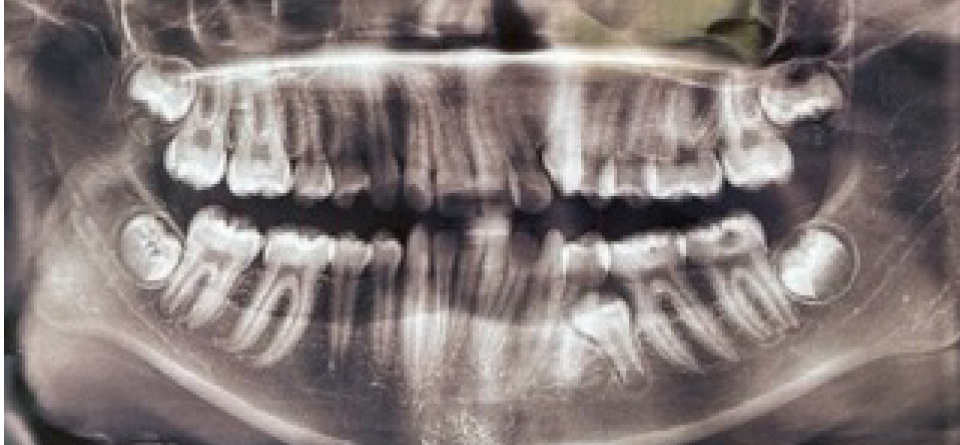

Результаты изучения анамнестических данных показали, что причиной односторонней ретенции вторых премоляров, как на верхней, так и нижней челюсти, было преждевременное удаление вторых молочных моляров на одной из сторон, которое отмечались практически у всех обследованных, что способствовало ретенции второго премоляра (рис. 2).

Рис. 2. Ортопантомограмма у пациентки с ретенцией второго нижнего премоляра слева